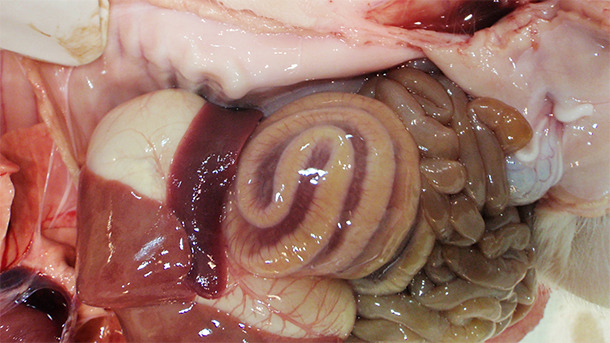

Les lésions associées à l’ICD sont essentiellement concentrées dans le gros intestin. L’œdème du mésocolon (Figure 1) est la lésion macroscopique classique observée dans les cas d’ICD. Toutefois, cette lésion n'est pas pathognomonique; Yaeger et al ont montré que l'œdème du mésocolon chez les porcelets n’est pas un bon prédicteur de toxines de C. difficile (Yaeger et al., 2007). L'examen histopathologique des animaux atteints a révélé une colite ulcérative fibrinopurulente multifocale ou localement étendue (Figure 2).

Figure 1. L'œdème de mésocolon est une lésion typique des cas d’ICD